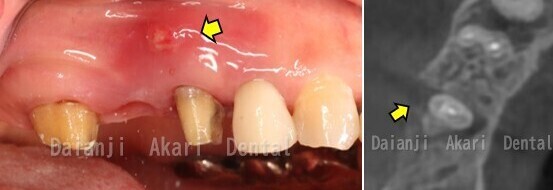

症例1

術前

まず、インプラント手術ができるか診断するため、口腔内の状態・レントゲン撮影を行います。

診断の結果、インプラントを入れるには骨の量も少なく、歯肉の量も少ないことがわかりました。このままインプラントを入れても長持ちできないと判断し、骨を増やす処置(骨造成術)と歯肉を増やす処置(遊離歯肉移植術)もおこなうこととしました。

骨造成

インプラント手術を行いました。同時に骨造成術もおこなっています。

術前のCT撮影でシミュレーションをおこない、手術後にもCT画像で安全にインプラントが入っているか確認します。黄色い矢印のところが骨造成部位になります。